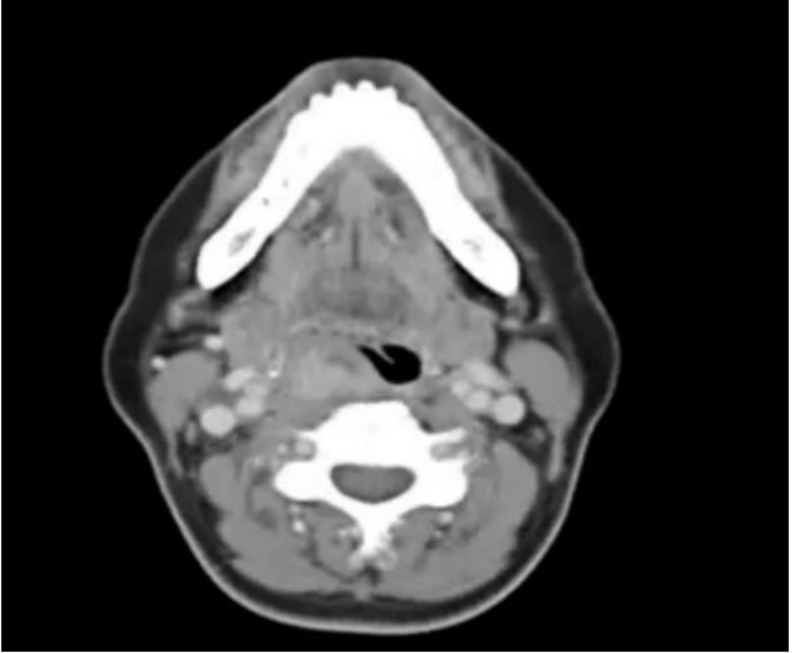

Case reports: We describe a novel case where primary papillary thyroid carcinoma (PTC) was found after a trans-oral excision of a tumor containing ectopic thyroid tissue at the posterior pharynx, an area not known to be a location for ectopic thyroid. Delays due to the COVID-19 pandemic resulted in regional cervical metastases and multifocal PTC. The female patient successfully underwent total thyroidectomy, selective cervical and central lymph node dissection, followed by adjuvant radioactive iodine ablation, with no evidence of distant metastases.